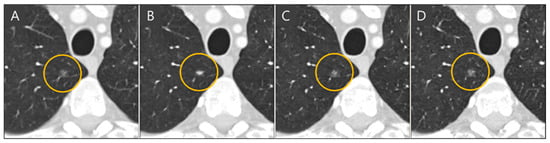

Lung nodule volumes measured in thick-slice, generated thin-slice, and thin-slice CT were categorized according to Lung-RADS v2022. Confusion matrices illustrating the classification outcomes and corresponding categorization definitions are presented in Figure 9 and Table 3, respectively. There were 31 misclassifications between the thick-slice and thin-slice CT, whereas only 8 misclassifications occurred between the generated thin-slice and thin-slice CT. Therefore, the agreement of lung nodule categorization with reference thin-slice CT images increased by 74 percent.

Figure 9. Confusion matrix of Lung-RADS v2022 lung nodule classification for (A) thick-slices–thin-slices CT pair and (B) generated thin-slices–thin-slices CT pair.